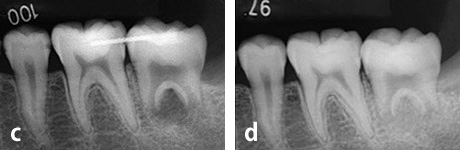

c : 移植直後

d : 移植後3ヶ月